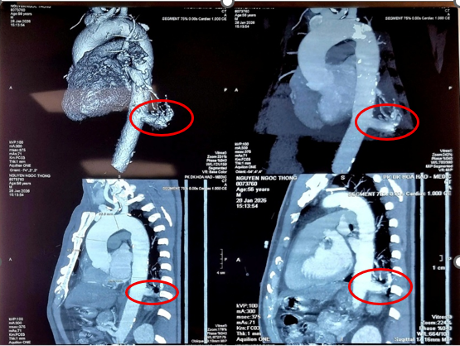

Tại Bệnh viện Bình Dân, ông được chẩn đoán mắc phổi biệt lập nội thùy với khối kích thước 23 mm × 26 mm. Đáng chú ý, động mạch nuôi khối này xuất phát trực tiếp từ động mạch chủ xuống với đường kính lên tới 17 mm – một kích thước rất lớn và đầy rủi ro nếu người bệnh không được điều trị.

Kết quả chụp MSCT ngực cho thấy phổi biệt lập nội thùy trong thùy dưới phổi trái, có nhánh mạch máu nuôi lớn xuất phát từ động mạch chủ ngực, rất nguy hiểm